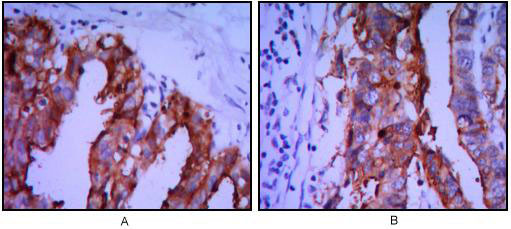

Supportive validation

- Submitted by

- Aviva Systems Biology (provider)

- Main image

- Experimental details

- Immunohistochemical analysis of paraffin-embedded ovarian cancer (A), stomach cancer (B) using ALPP mouse mAb with DAB staining.